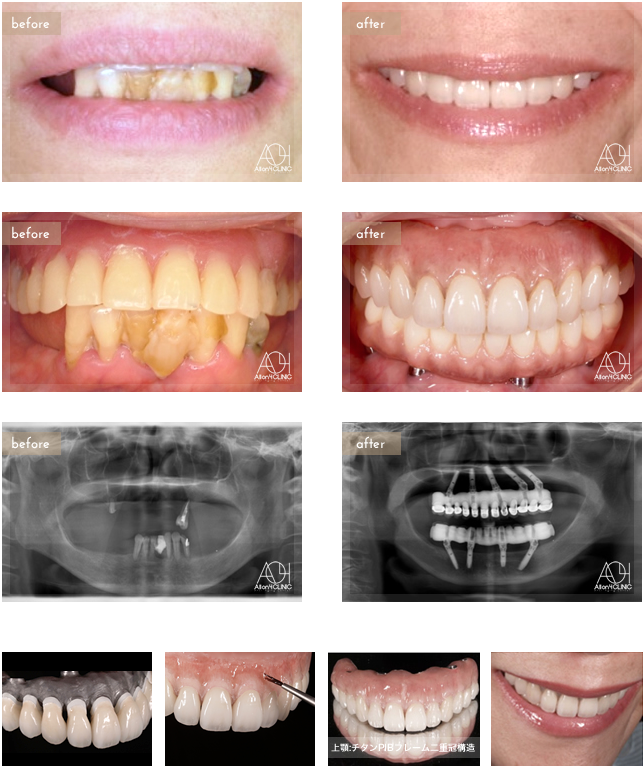

Age : 61

Sex : Female

Treatment : 2010

-Maxilla All-on-4

- Under All-on-4

上顎は5本のインプラントを埋入。下顎はAll-on-4。上顎上部構造は二重冠構造(歯肉:アクリリックレジン 歯:セラミック)を採用。下顎はハイブリッドタイプ(歯肉:ハイブリッドセラミック 歯:ハイブリッドセラミック)。 上顎はチタンPIBフレーム。下顎チタンPIBフレーム。